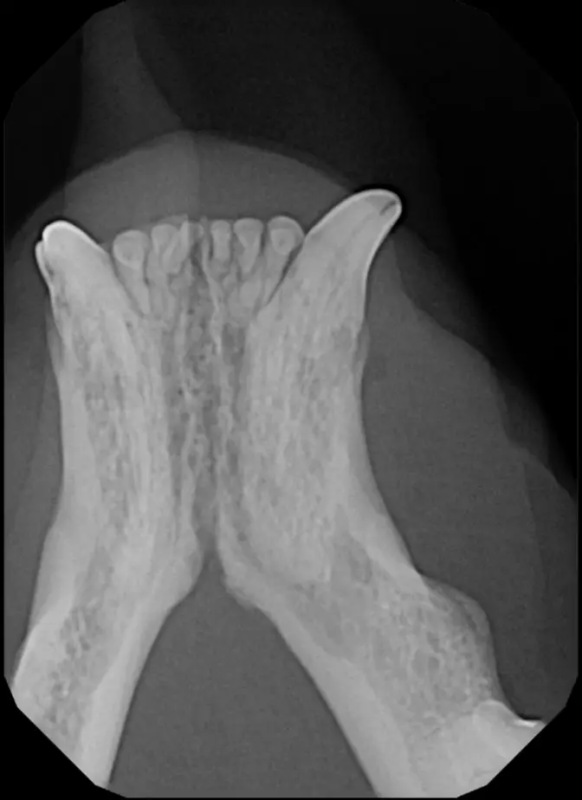

Surgical Extraction of Diseased Teeth

Periodontal disease is extremely common in dogs and cats. Over 80% of dogs and cats over two years of age have some degree of periodontal disease. Periodontal disease is best prevented by yearly professional dental cleanings starting at two years of age and at home brushing at least three times weekly. Brushing should begin at a very early age to allow your new pet to get used to regular brushing. In severe cases of infection or periodontal disease, the teeth may need to be surgically extracted. Extractions should always involve x-rays of the tooth first, as many teeth have multiple roots or may be diseased below where the eye can see. Extracting larger teeth in animals requires oral surgery, equivalent to removing wisdom teeth in people. It is vital that all of the tooth and roots be removed for the periodontal infection to resolve. In cases of important teeth with mild to moderate periodontal disease, multiple periodontal treatments can be offered to help save these teeth.

Tooth resorption is a disease process where the body begins to break down the adult tooth. It is widely known to occur in cats but can also occur in dogs. In cats these lesions are thought to be inflammatory, while in dogs they can be more of a replacement resorption process. These lesions can be very painful and should be treated, generally with extraction depending on the type of resorption that is occurring. The disease can be progressive and affect many teeth over several years. It is important to have regular checkups and yearly dental cleanings to monitor for these lesions.